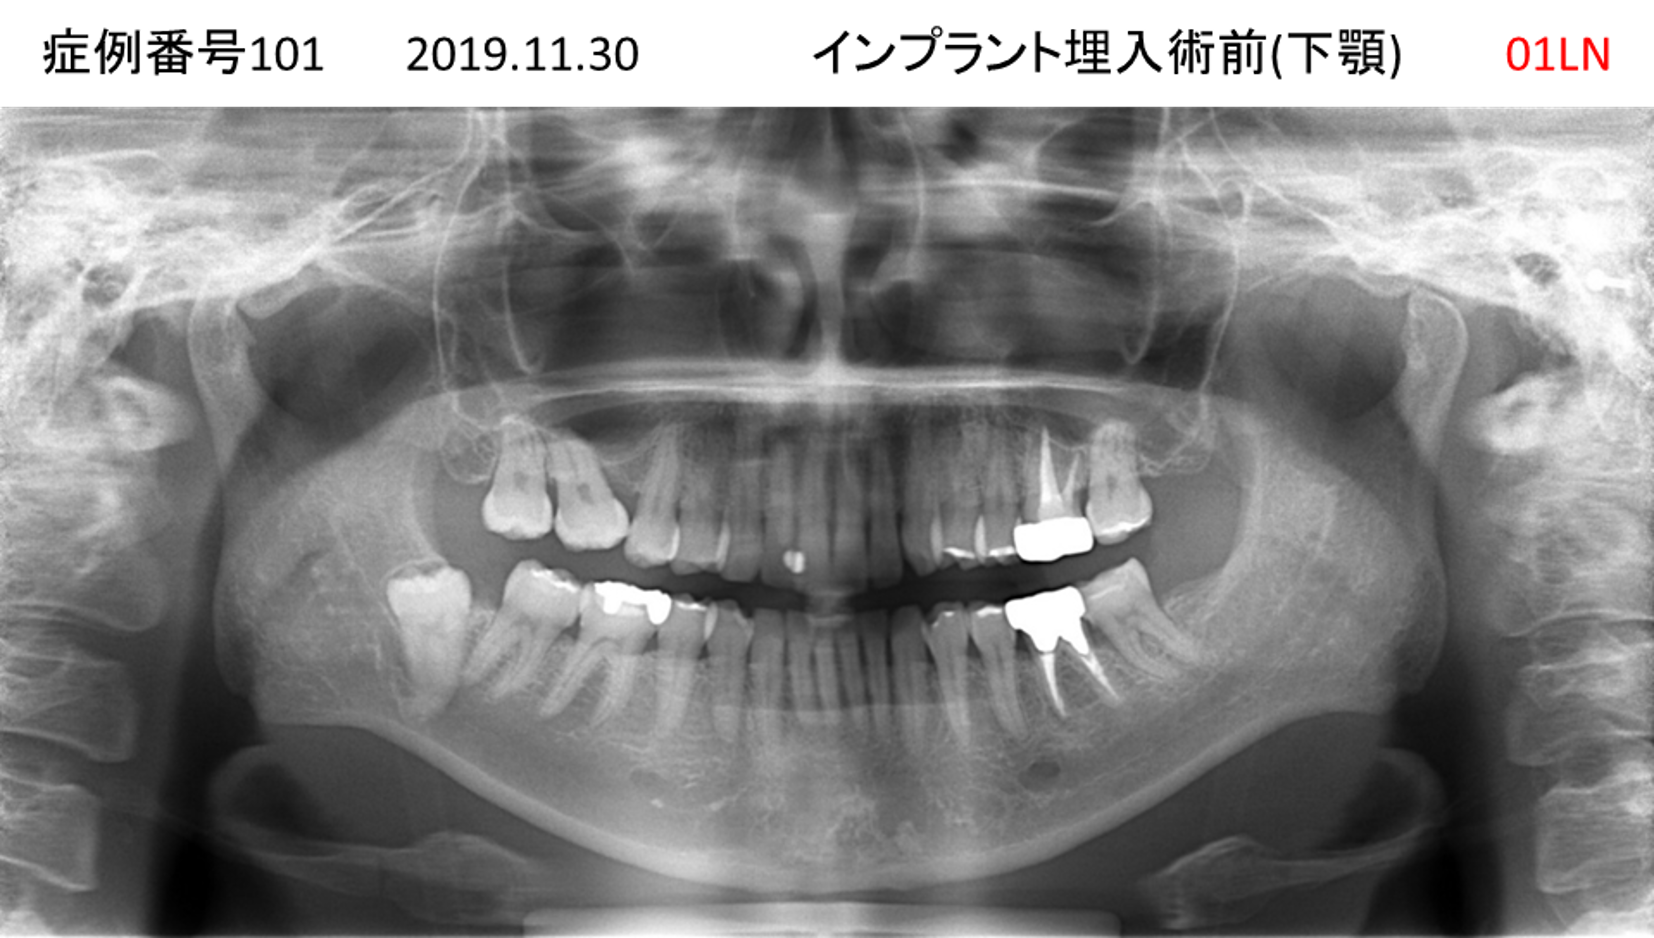

噛めない/固いものが食べられない患者様のインプラント症例

| 治療名称 |

インプラント |

| 治療費用 |

340万円+税 |

| 治療期間 |

6か月 |

| 患者さんの症状(主訴) |

噛めない。固いものが食べられない。 |

| 治療内容 |

サイナスリフト、抜歯即時インプラント |

| 治療結果 |

何でも食べられる。食事に困らない。 |

| 治療の注意点(リスク/副作用) |

インプラントが壊れたら再治療が必要 |